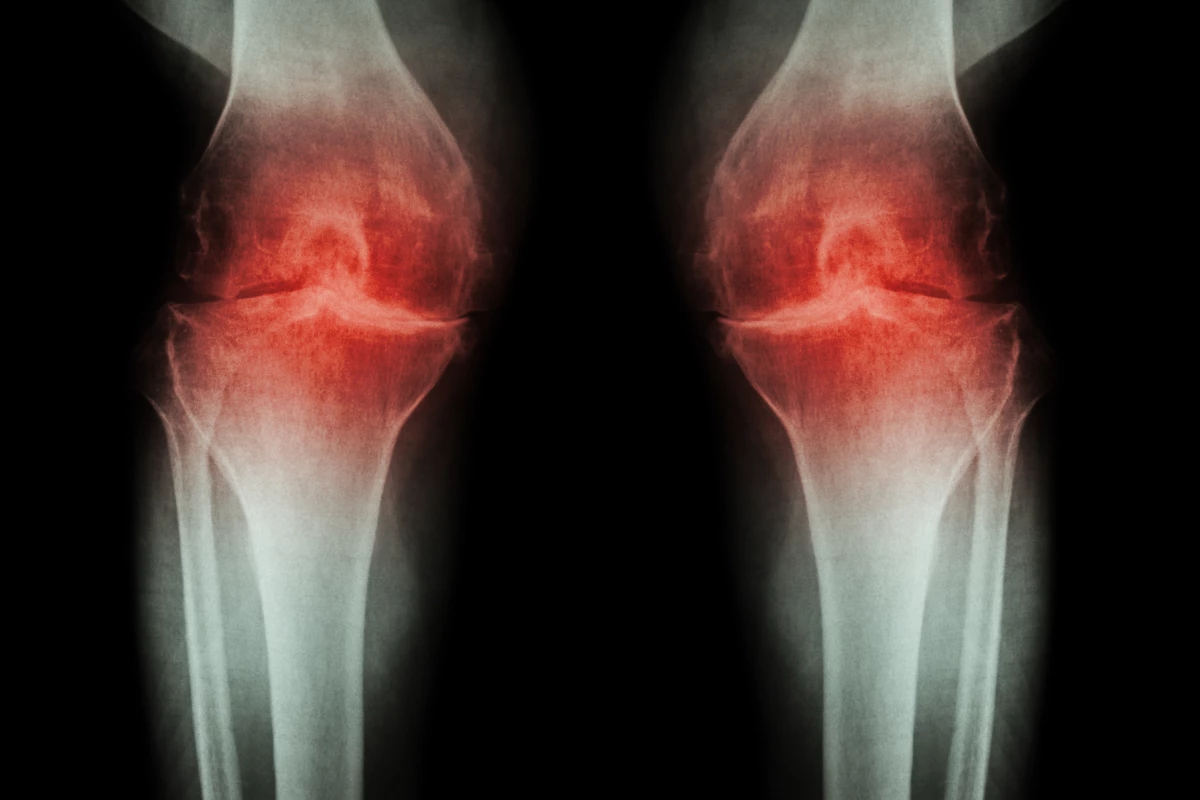

Popular anti-inflammatories linked to worse osteoarthritis progression

New data presented at the Radiological Society of North America's annual meeting suggests long-term use of non-steroidal anti-inflammatory drugs (NSAIDS), such as naproxen or ibuprofen, can be associated with hastened progression of osteoarthritis symptoms. The researchers are cautious to stress the link is still observational and more work needs to be done to understand how these drugs could be linked to worsening arthritis inflammation.

The new research, led by Johanna Luitjens from the University of California, San Francisco, focused on the association between long-term NSAID use and an arthritis symptom called synovitis. The synovial membrane is the connective tissue that lines joints like our knees or wrists, and synovitis is when that membrane becomes irritated and inflamed.

The researchers recruited over 1,000 subjects with moderate to severe osteoarthritis of the knee. Around one-quarter of the cohort received sustained NSAID therapy for over a year, while the remaining participants were not treated with the common painkillers. Each participant completed a knee MRI at the beginning of the study, and again four years later.

Evaluating a variety of MRI biomarkers of synovitis the researchers saw no long-term benefits from NSAID use over the four-year study period. In fact, markers of joint inflammation were unexpectedly worse in the NSAID group at the end of the study, compared to those not taking the anti-inflammatory drugs.

“In this large group of participants, we were able to show that there were no protective mechanisms from NSAIDs in reducing inflammation or slowing down progression of osteoarthritis of the knee joint,” said Luitjens. “The use of NSAIDs for their anti-inflammatory function has been frequently propagated in patients with osteoarthritis in recent years and should be revisited, since a positive impact on joint inflammation could not be demonstrated.”